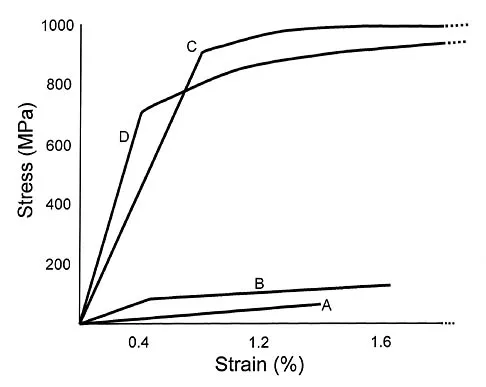

Why is tendon considered an anisotropic material?

Explanation